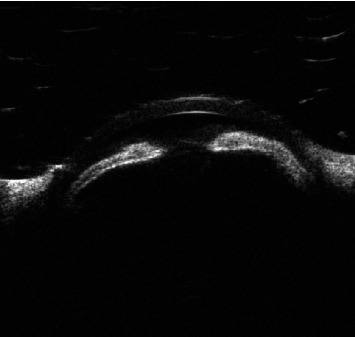

Abstract Image